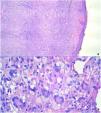

We proceeded the complete excision of the tumor. Histopathological study identified a nodular dermal proliferation with xanthomized histiocytes, foreign body-type multinucleated giant cells and Touton multinucleated cells, along with scattered lymphocytes, plasma cells and eosinophils (Fig. 3a and b). Immunohistochemistry appointed positive stains for CD68. S100 and CD1a were absent. BRAF-V600E mutations analysis through real-time polymerase chain reaction (PCR) was negative. Laboratory investigation revealed no abnormalities in routine blood examination parameters, triglyceride levels, liver function or renal function. The tests confirmed the diagnosis of adult xanthogranuloma, and there was clinical improvement after surgical removal. The patient maintains dermatological follow-up with no injury recurrence.

Diagnostic confirmation is made through skin biopsy. Histopathological analysis identifies dense dermal histiocyte infiltrate and Touton giant cells, which are multinucleated cells, with homogeneous eosinophilic cytoplasmic center and peripheral xanthomatization.3 Immunohistochemistry is also important to define diagnosis and shows positive stains for Factor XIIIa, CD68, CD163, CD14, and fascin. Stains for S100 and CD1a, specific for Langerhans cells, are negative.9 In cases with atypical histology features or immunohistochemistry suggestive of xanthogranuloma and Langerhans cell histiocytosis (LCH), the investigation of BRAF-V600E mutations is recommended. BRAF-V600E mutations have been described in LCH and can identify LCH coexisting with xanthogranuloma.10 In this case report, this oncogenic mutation was absent, reaffirming the xanthogranulomatous nature of the tumor.